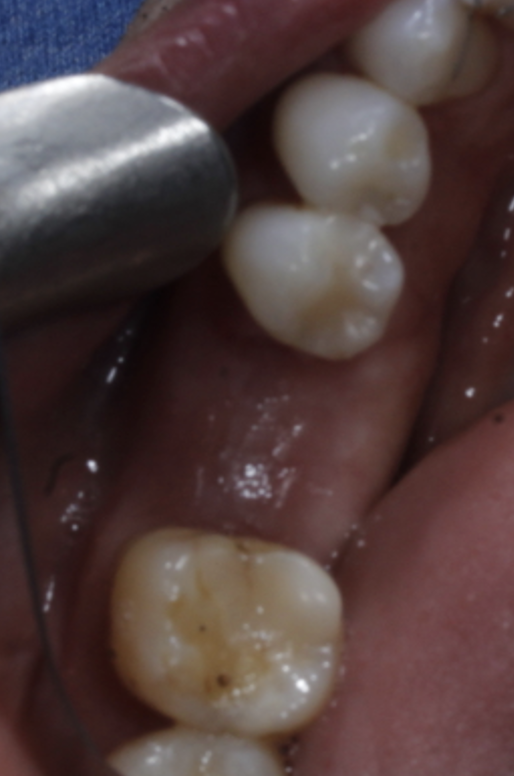

( after 3 months, implant was uncovered but the buccal cervical bone is missing , there is no denture use at all and the buccal wall just disappeared. there was no bone graft or membrane used when the implant was placed)